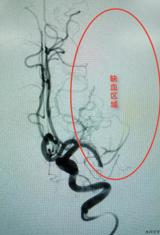

近日,我院神经介入团队成功开展一例脑栓塞机械取栓术,挽救了一名76岁“醒后卒中”患者的生命。该例手术也是本地区自主完成的首例脑栓塞机械取栓术,这意味着我院神经介入技术日益精进。 3月11日凌晨,新丰镇的陈大爷在起床的时候,身体突然出现了异常状况,不仅讲不出话来,右侧肢体完全不能动,持续约3个多小时,家人...2023-03-15